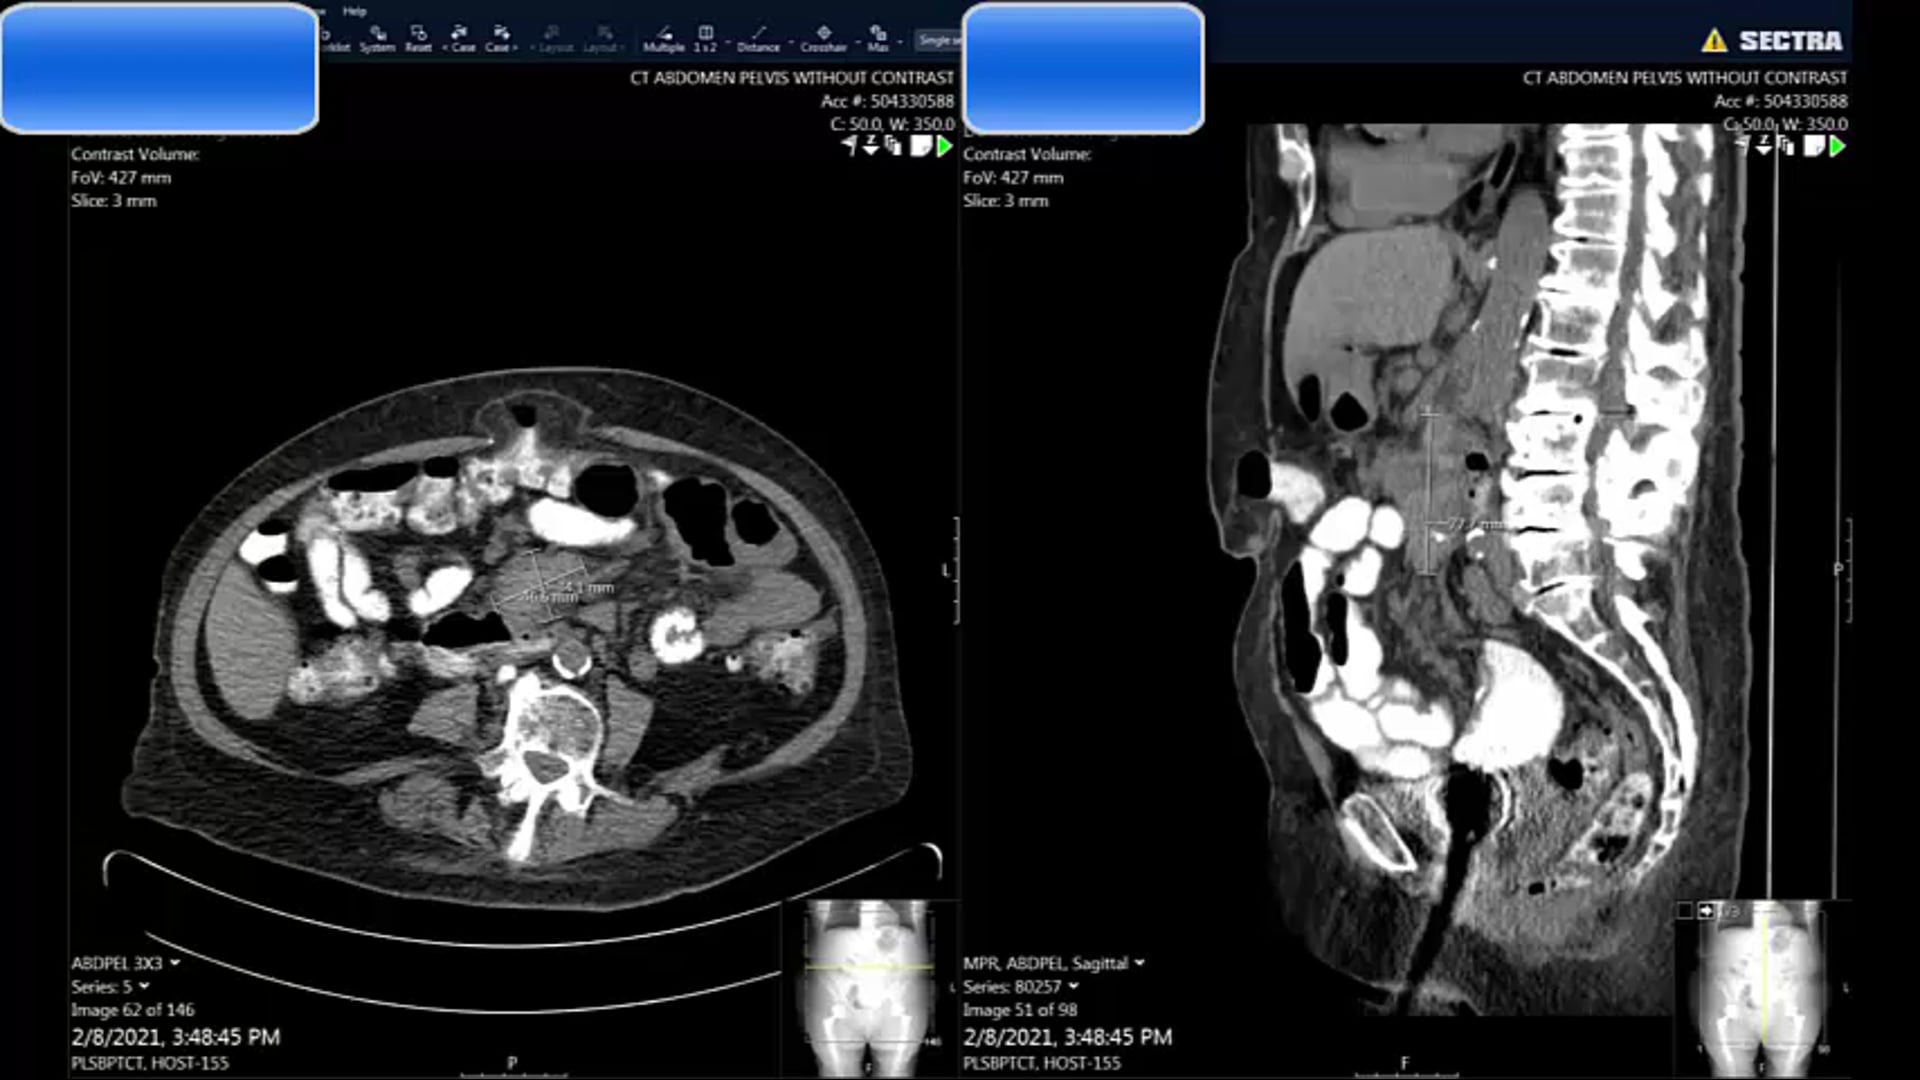

63 yo Anal T3

Large LN adjacent to tumor